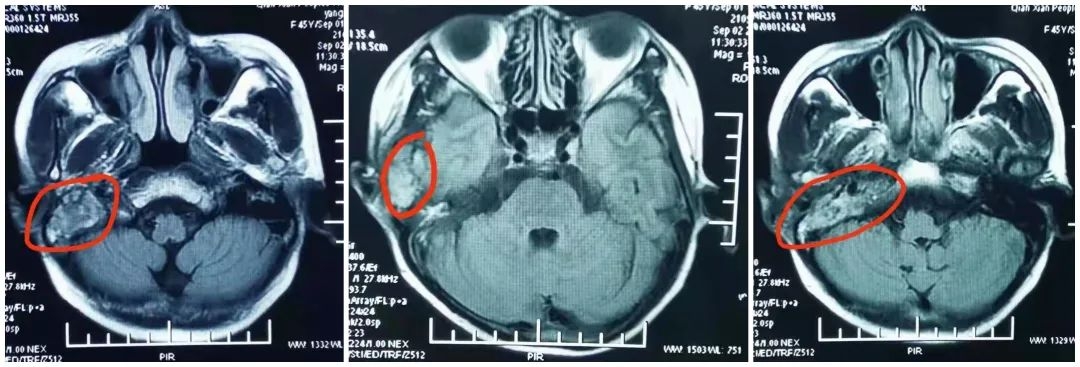

患者为46岁女性 , 21年前行右腮腺混合瘤手术 , 因肿瘤复发 , 分别于2001年、2007年、2016年多次进行手术治疗 , 术后病理显示”右腮腺混合瘤恶变” , 因为病情需要先后经历了多次放、化疗 。 不久前 , 患者行局部放疗后肿瘤再度复发 , 并伴有颅骨及颞叶转移 , 受疼痛困扰的她来到了咸阳市中心医院就诊 , 因无法耐受再次放疗 , 经过肿瘤三科医疗团队周密讨论 , 综合考虑并与家属沟通后 , 最终决定为患者实施颅内肿瘤放射性粒子植入术(碘125粒子) , 术毕患者饮食活动未受影响 , 留院观察一晚后于次日晨出院 。